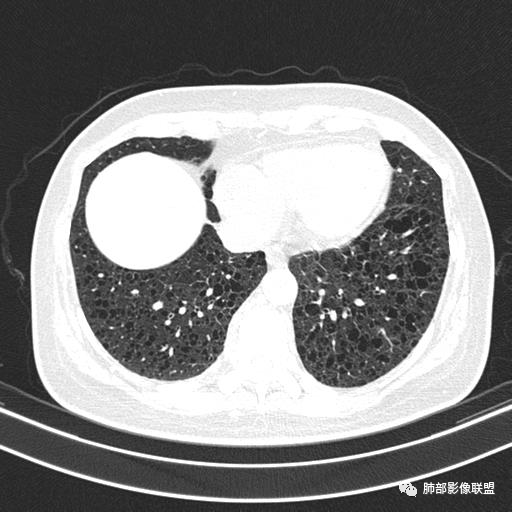

双肺弥漫囊腔,累及肋膈角,囊腔形态相对规则单一。

CT平扫示双肺弥漫分布大小不等囊状薄壁透光区,无内、中、外带分布差异,间质稍示增厚。拟LAM

中年女性育龄期妇女,咳嗽气喘,无吸烟史,有苯吸入史。影像:双肺弥漫均匀小囊腔,无明显分布优势,囊腔形态欠规则,壁薄,部分囊腔边缘血管征,伴双肺弥漫磨玻璃影,无结节,考虑lam,鉴别苯中毒肺损伤,囊腔多有分布优势,小叶中心分布为主,形态规整等

女,46,活动性气喘1年。苯吸入史半年。胸部CT:两肺弥漫囊腔,上至肺尖,下至肋膈角,形态类似小囊腔。考虑:LAM,鉴别LIP,BHD,PLCH等。

CT表现:双肺弥漫大小不等的薄壁囊腔,囊壁<2mm,外形规则,血管影多位于囊腔周围,囊腔之间肺组织正常,随着疾病进展到晚期,囊腔变大、增多,不可胜数,囊腔可融合成较大的囊,与肺气肿相似,形成间质性肺纤维化。部分病例可出现结节影。